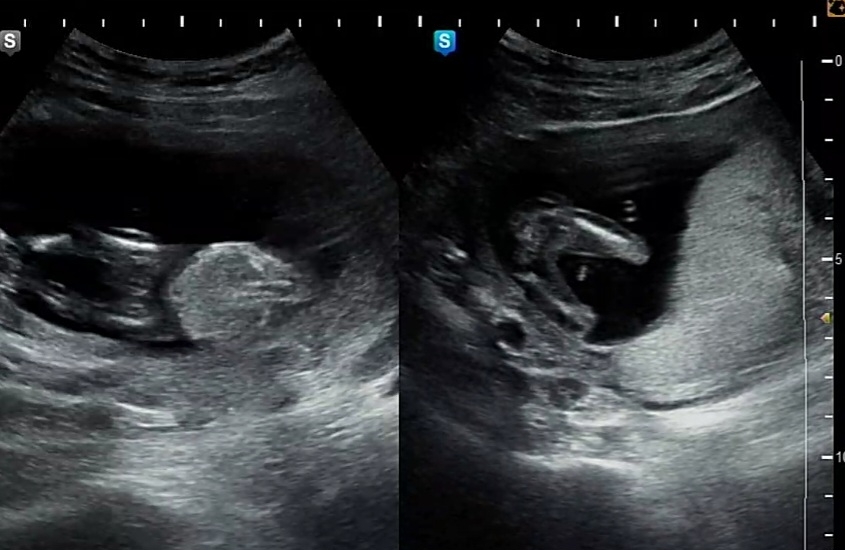

설전에 미리알고싶어서 15주차갔는데 바로 봐주시더라구요~ 아무것도없다고 90% 딸이라고하시길레 언제 확실하냐니까 그건 낳아봐야 안다네요ㅋㅋㅋ 그래도 90프로라하셔서 기쁜마음으로 원피스 하나 샀답니다😆 사람 욕심이라고 성별알고나니 빨리 태동느끼고싶네요ㅎㅎ